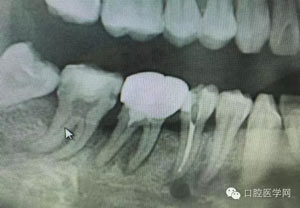

病例1:患者迫切希望保留自己的這一顆牙齒,根尖周陰影比較大,二度松動(dòng).而且旁邊有種植修復(fù)體,和患者溝通好后,治療好后觀察一個(gè)月后冠修復(fù),因?yàn)橛蟹N植的后期修復(fù),所以有了機(jī)會(huì)觀察,術(shù)后三個(gè)月和術(shù)后四個(gè)月,根尖恢復(fù)的還算不錯(cuò),希望能夠繼續(xù)觀察下去.這樣子的病例,做的時(shí)候我們一定要非常的小心,和患者要有充分的溝通以及不同科室的溝通然后決定怎么樣做比較好,假如就是出現(xiàn)了問(wèn)題,到時(shí)候我們也比較好處理些,免得我們自己到時(shí)候不好收?qǐng)觥?/span>